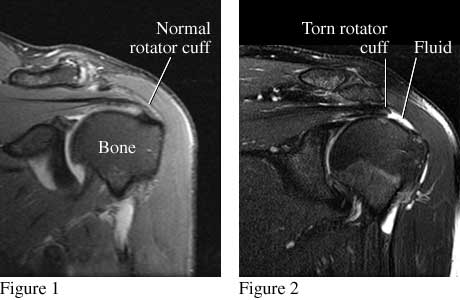

MRI images of torn rotator cuff.

Figure 1 is a front view of the shoulder that shows a normal rotator cuff. Figure 2 is a similar view that shows a torn rotator cuff.